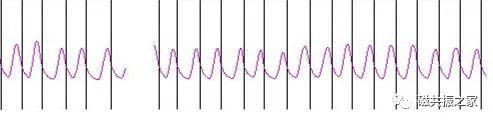

上腹部需采用呼吸门控扫描,门控安置方法:观察患者胸前肋下区域呼吸幅度最明显的位置,安置呼吸门控,使其显示的呼吸幅度波形超过上下位置的30%。

1.高磁场对运动更为敏感,其伪影也更重。 在腹部扫描中,应注意对呼吸的控制。上腹部扫描中主要是解决蠕动和呼吸运动伪影的问题,目前上腹扫描方式:

以最常见的屏气(T1WI序列推荐)和呼吸触发(T2WI序列推荐)的方式扫描能效最高,应根据被检者的当前状态,充分利用MRI每个序列的特点和临床优势,合理的序列组合为临床提供必要的影像学信息。

2.不建议被检者刻意控制其呼吸频率,应保持平静、放松的状态。